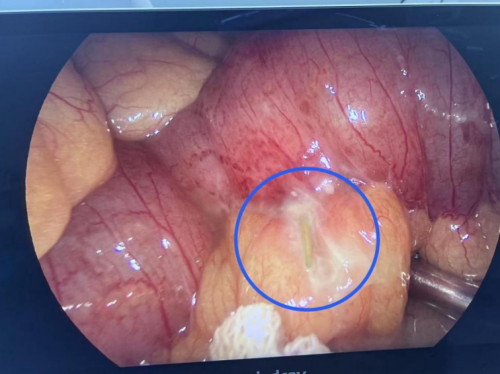

考虑到传统开腹手术创伤大、恢复慢,为减少患者痛苦,急诊外科副主任邵启兵带领团队经过充分评估,最终决定经腹腔镜下行异物取出+肠穿孔修补术。手术过程中,邵启兵副主任精准定位异物位置并成功取出一长约6CM的尖锐甲鱼骨,并对穿孔部位进行精细修补,严密防范肠瘘等并发症的发生,手术顺利完成。术后患者转入EICU进行严密监护治疗,2天后患者病情趋于稳定,顺利转入急诊综合病房,现患者肠道功能已基本恢复正常,择日出院。

术中可见回肠部有一尖锐的鱼骨导致肠穿孔